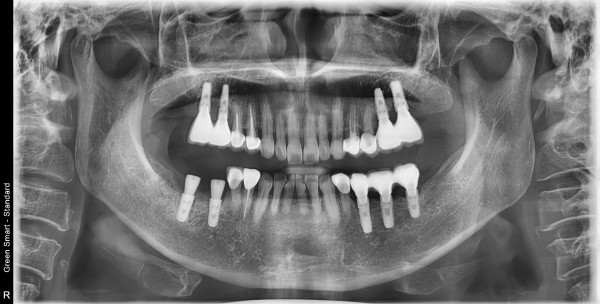

목록 글쓰기 임플란트 임플란트 재식립 사례 페이지 정보 작성자최고관리자 작성일2025-07-18 본문 타치과에서 실패한 임플란트 재식립 사례_365드림치과병원 댓글 0 댓글목록 등록된 댓글이 없습니다. 치료사례 카테고리 전체임플란트치아교정심미보철기타 Total 9건 1 페이지 게시물 검색 검색대상 제목+내용 제목 내용 작성자 검색어 필수 글쓰기 9 BEFORE AFTER 클릭 해주세요. 앞니 벌어짐 치아교정 8 BEFORE AFTER 클릭 해주세요. Smilefit 심미보철 심미보철 7 BEFORE AFTER 클릭 해주세요. Smilefit 심미보철 심미보철 6 BEFORE AFTER 클릭 해주세요. 전체교정 치아교정 5 BEFORE AFTER 클릭 해주세요. 전체치아교정 치아교정 4 BEFORE AFTER 클릭 해주세요. 전체 치아교정 치아교정 3 BEFORE AFTER 클릭 해주세요. 전체임플란트 임플란트 열람중 BEFORE AFTER 클릭 해주세요. 임플란트 재식립 사례 임플란트 1 BEFORE AFTER 클릭 해주세요. 하악 임플란트,치조골이식 임플란트 네이버 예약 협력기관 예약 MOU 카카오톡 상담 네이버 상담 + × TOP